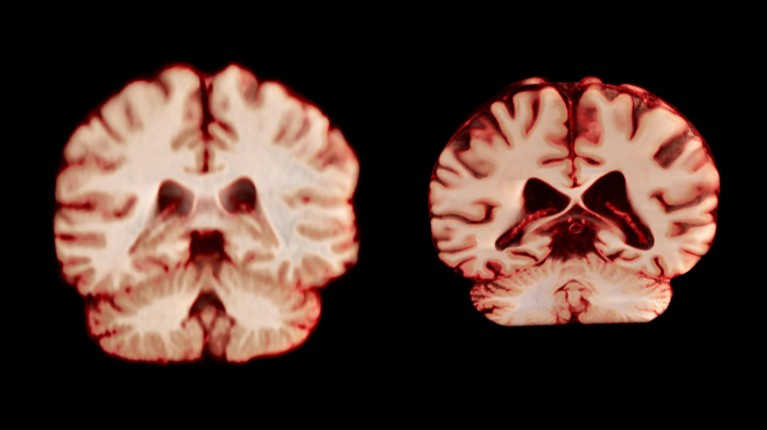

男性大脑萎缩速度快于女性,但女性阿尔茨海默病患病率是男性两倍

10月13日发表在PNAS的一项研究表明,随着年龄增长,男性大脑多个区域的萎缩速度均超过女性。然而这一发现似乎并未解开女性阿尔茨海默病患病率更高的谜团。

年龄是阿尔茨海默病最大的风险因素。一个长期困扰学界的现象是,被诊断患有阿尔茨海默病的女性几乎是男性的两倍。为了探究背后的原因,研究人员一直致力于寻找与年龄相关的大脑性别差异。“如果我们发现女性的大脑衰退得更严重,那或许可以解释为何她们的患病率更高,”新研究的共同作者、奥斯陆大学的博士生Anne Ravndal表示。

健康大脑(左)和受阿尔茨海默病影响的大脑。| 图片来源:Anatomical Travelogue/SPL

在这项研究中,团队分析了来自4726名参与者超过12500份磁共振成像(MRI)大脑扫描数据。这些参与者均未患阿尔茨海默病或任何认知障碍。研究人员对每位参与者进行了至少两次扫描,平均间隔三年,以追踪他们大脑结构随时间的变化。研究重点关注了灰质厚度以及与阿尔茨海默病相关的关键脑区(如负责记忆的海马体)的大小。

结果与研究者的预期恰恰相反,总体上,男性大脑在更多区域表现出更快的体积萎缩。例如,负责处理触觉、痛觉、温度以及身体位置和运动的中央后回,男性年均萎缩2.0%,而女性为1.2%。澳大利亚悉尼大学的临床神经心理学家Fiona Kumfor评论说,这表明男性的大脑老化速度可能比女性更快,也与男性预期寿命较短相符。

这一结果对解释阿尔茨海默病的性别差异提出了挑战。澳大利亚莫纳什大学的研究员Amy Brodtmann指出,如果大脑老化是导致女性患病率高的主要原因,那么研究本应观察到女性在海马体和楔前叶等记忆相关区域出现更严重的萎缩,但事实并非如此。

Kumfor表示,这一发现并不完全令人惊讶,因为神经退行性疾病本身就极其复杂。“仅仅观察与年龄相关的大脑萎缩,不太可能解释其背后的复杂性。”她认为,要真正理解这类疾病,需要对已患病的阿尔茨海默病患者进行长期的跟踪研究,以比较他们的大脑如何随时间变化。

专家也指出了该研究的一些局限性。例如,研究的参与者大多受过高等教育,而教育被认为是阿尔茨海默病的保护因素之一,这意味着样本可能无法完全代表普通人群。此外,数据集还缺少其他可能影响患病风险的因素,如种族以及女性进入更年期的年龄等。

有趣的是,研究作者补充说,一旦他们根据受教育水平对数据进行调整,男性大脑在某些区域的衰退速度便不再显著快于女性。而当他们比较预期寿命相同的男性和女性时,两组的大脑衰退速度也变得相似。